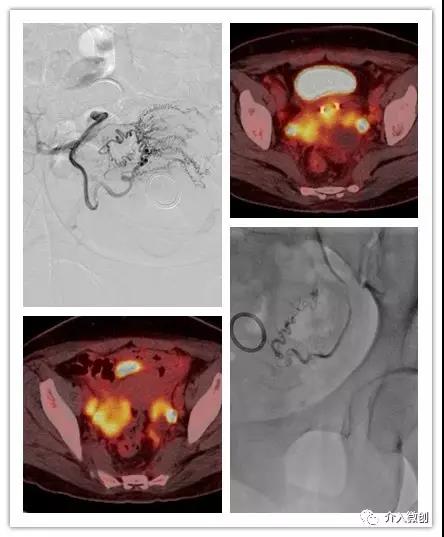

典型病例

中年女性,因宫颈癌晚期侵犯宫体,导致持续阴道出血,行DSA下双侧子宫动脉化疗栓塞治疗,术后阴道出血迅速缓解,生活质量明显改善。

宫颈癌化疗栓塞治疗